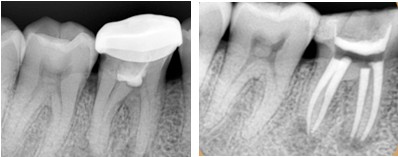

一般情况下,我们牙齿的蛀牙会经历这几个过程:大家看下图↓↓↓

一般情况下到了深龋,并伴有疼痛,说明蛀牙已经影响到牙髓腔了,如果牙髓被感染了就要进行根管治疗。并不是医生想要唬你。如果还没到达深龋,没有感染牙神经,一般只需要进行去腐后常规补牙即可。